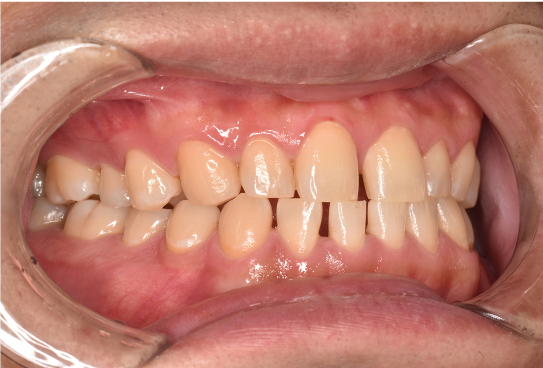

general 30代男性「タバコのヤニが気になる」縁上歯石・着色を除去し、その後歯周治療を行った症例

治療後

| 行ったご提案・治療内容 | 初診時はブラッシング方法などセルフケアについて説明を行い、縁上歯石・着色の除去を行いましました。 歯肉の炎症がある程度落ち着いたところで、後日再評価を行い歯周治療へ移行しました。 |

| 術後の経過・現在の様子 | 綺麗になったと喜んでいただき、この状態を保てるようセルフケアにも力を入れてくださっています。3ヶ月に一度の定期検診にも通っていただいています。 |